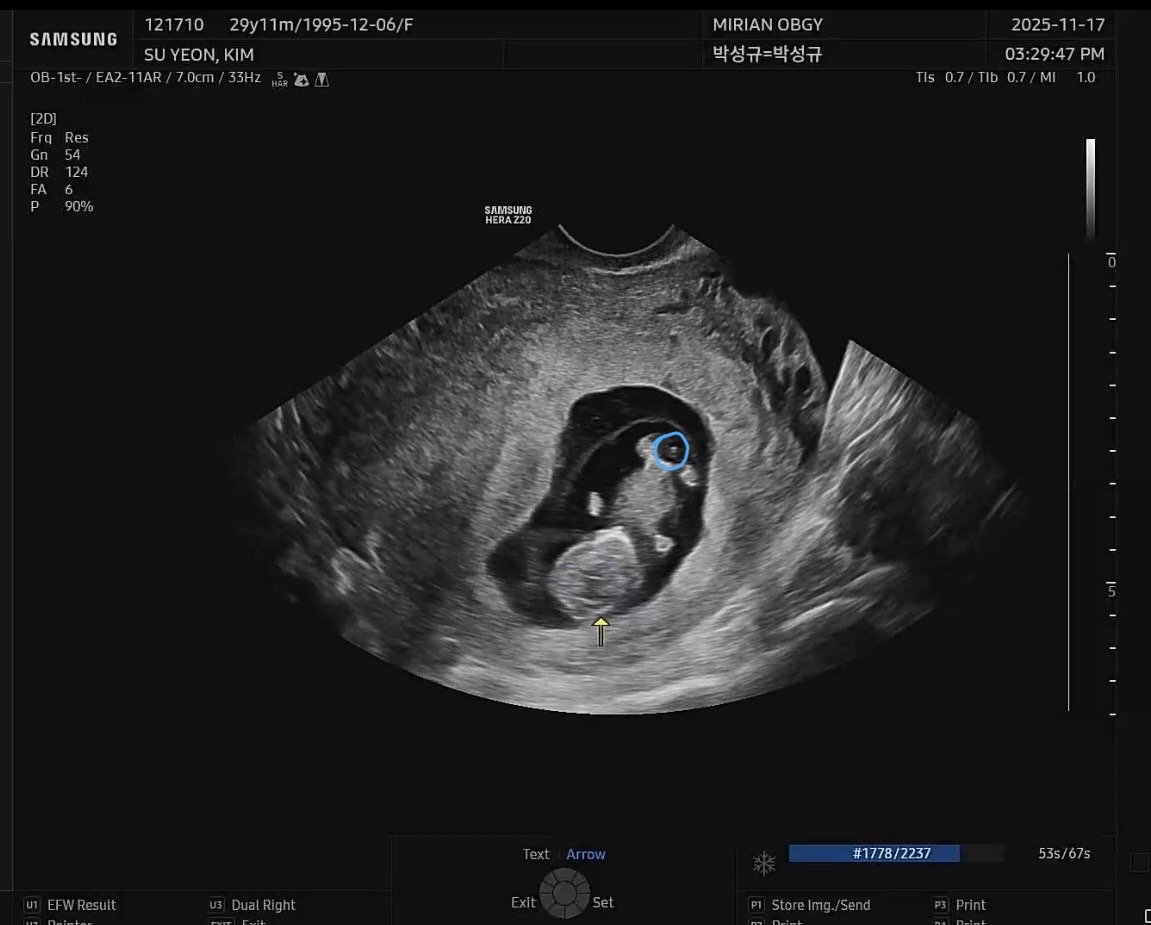

9주 5일 초음파

9주 5일 초음파 사진인데요 딸은 딱 세갈래로 갈라진다던데 이거 보더니 형님이 아들같다해서 그런데 아들인거같나요?